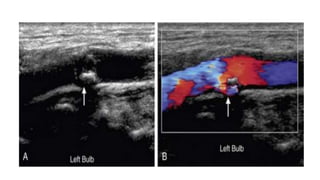

• #39  Hypoechoic plaque. A, Longitudinal gray-scale image does not demonstrate the hypoechoic plaque in the left carotid bulb. B, However, the hypoechoic plaque (arrow) is clearly outlined by color flow on the color Doppler image.

• #40 Irregular plaque. Longitudinal gray-scale (A) and color Doppler (B) images of the left carotid bulb demonstrate flow (arrow) undermining a focus of echogenic, shadowing plaque.

• #41 Ulcerated plaque. Gray-scale (A) and color Doppler (B) images demonstrating a divot or pit (arrow) within a large area of echogenic plaque with an irregular surface. This probably represents an ulcer.